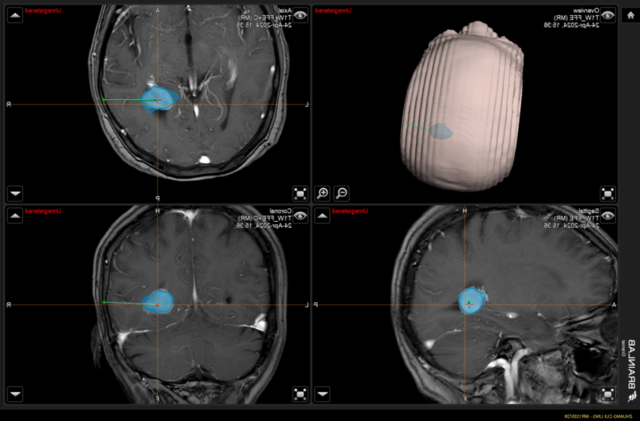

▲术中神经导航模拟肿瘤位置,精准定位,计算最优路径

经神经导航的辅助,选取微创小切口,完整切除肿瘤,术中出血少,对功能区保护满意。